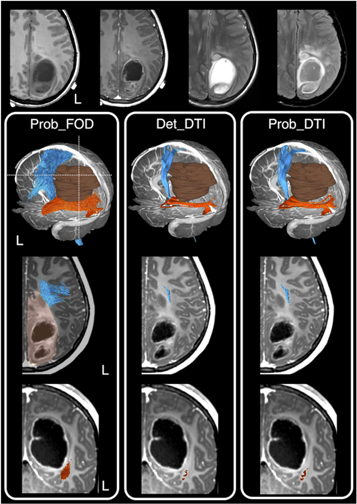

In a recent survey conducted from 36 out of all 40 neurosurgical units in the UK and Ireland, 90% of the neurosurgical units use tractography regularly, and they are predominantly DTI-based reconstructions. Concerningly, many neurosurgeons remain unfamiliar with the underlying methods used to produce tractography visualisations (Toescu et al 2020). An alternative way to provide a snapshot of clinical practice is to look at relevant tractography surgical cohort reporting. An author-initiated PudMed-based search for relevant literature over the last 25 years, demonstrating the striking contrast between the advanced dMRI-informed tractography research and what is being utilised and published from the clinical neurosurgical practice. Overwhelmingly, 94.7% of neurosurgical publications utilised DTI-based tractography, with the remaining 5.3% of studies utilised higher-order dMRI modelling techniques. Importantly, although many of these studies recognised the limitation of DTI-based tractography, and emphasised the need to introduce more advanced methods, none had actually proceeded with furthering research and industry partnership, working towards translating advanced dMRI methodologies into neurosurgical practice (Kuhnt et al 2012, Bucci et al 2013, Farquharson et al 2013, Kuhnt et al 2013, Zhang et al 2013, Lim et al 2015, Mormina et al 2015, Ashmore et al 2020, Fekonja et al 2021). Figure 10 shows a clinical example of differences in tractography appearances based on the selected dMRI modelling and tracking techniques.

Figure 10. A clinical case example showing tractography reconstruction using a combination of different modelling techniques and tracking algorithms and the impact on pre-surgical planning and intraoperative image-guidance. This is an 11- year-old girl presented with early clinical features suggestive of raised intracranial pressure, referable to a large left parieto-occipital high-grade glioma (glioblastoma multiforme). The corticospinal tracts (in blue), and optic radiations (in orange), and the brain tumour segmentation (in brown) are shown. The dashed white lines are the approximate image planes for the axial and coronal MR images, which are displayed in radiological convention. Note both the deterministic and probabilistic DTI tractography (Det_DTI and Prob_DTI) lead to the impression of gaps observed between the tumour margins and both white matter tracts; and failure to reconstruct the lateral projections of the corticospinal tract (i.e. the 'too-few', false-negative tracking problem). The use of the probabilistic tracking algorithm only partially recovers some of the 'missing' lateral corticospinal tract fibres. Using these tractography images in surgery can lead to inadvertent surgical injuries to both fibre tracts and associated functional consequences. On the other hand, reconstructions using a probabilistic fibre orientation distribution based (FOD) technique (Prob_FOD), combined with carefully placed regions-of-interest based on anatomical priors, limit the 'too-many', false-positive tracking problem. The reconstructed fibre tracts are anatomically more plausible in their appearances and are abutting the tumour margins—a critical piece of information for surgical approach and resection of this tumour. Material acronyms: Det_DTI (deterministic tracking algorithm, diffusion tensor imaging model), Prob_FOD (probabilistic tracking algorithm, fibre orientation distribution based), Prob_DTI (probabilistic tracking algorithm, diffusion tensor imaging), L (left).

Download figure:

Standard image High-resolution imageNonetheless, there remains a pressing need to bridge the evidence-practice gap between dMRI-informed tractography research on the one hand and clinical neurosurgery practice on the other. Establishing close clinical, research, and industry partnerships are key to further translate these novel techniques into the clinical neurosurgery realm (more to this in Q&A 8).